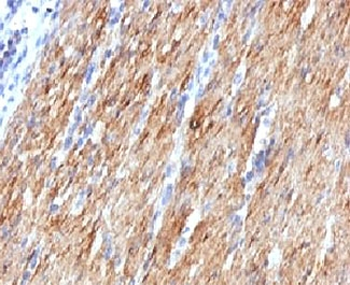

IHC: Formalin-fixed, paraffin-embedded human colon carcinoma stained with SMMHC antibody (MYH11/923).